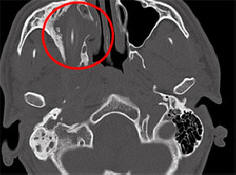

Някои заболявания и наранявания са толкова незабележими, че човек може да живее с тях години наред, без да ги подозира съществуване. Като американец, който отне почти две години изтичане на собствена мозъчна течност за хрема, германски гражданин успя да изживее 15 години с молив в главата, съобщава Spiegel. Както казаха представителите на университетската болница Аахен, Северен Рейн-Вестфалия, 24-годишен афганистанец произход дойде при тях за помощ още през 2011 година. млад лицето се оплаква от постоянни главоболия, настинки и влошаване зрение в едно око. Дълго време лекарите не можеха да разберат какво се случва. не са направили компютърна томография. Оказа се, че в главата ми пациентът през цялото това време беше 10-сантиметров молив. Той е разположен директно над десния гнездо на младия мъж и поставен върху него налягането. Германец, който искаше да остане анонимен, не можа да обясни откъде идва моливът в главата му, но по-късно си спомня колко неуспешно падна в детството. Лекарите извадиха чуждо тяло от главата млади мъже и той скоро се съвзе. Само в края на май, след почти година след операцията лекарите решиха да се посветят на този случай отделна конференция, благодарение на която репортерите научиха за нея. Това не е първият път, когато човек се справя от дълго време живейте с чужд предмет в тялото си. И така, през 2007г възрастна немска жена, страдаща от главоболие и кървене от носа, махнаха молив, който беше там от 50 години.